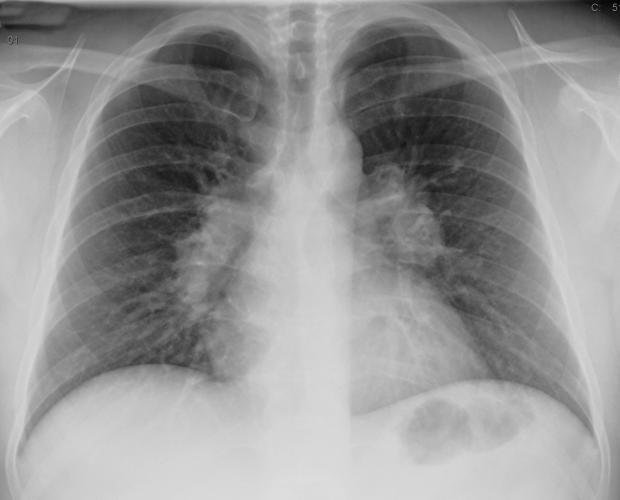

Саркоидоз легких представляет собой системное заболевание, характеризующееся образованием гранулем в легочной ткани. Врачи отмечают, что это заболевание может проявляться различными симптомами, включая кашель, одышку и грудную боль. Часто саркоидоз легких диагностируется случайно при рентгенологическом исследовании, когда обнаруживаются характерные изменения в легких.

Проведение бронхоскопии и биопсии обнаруживают различные признаки саркоидоза – расширенные сосуды в устьях (корне) долевых бронхов, увеличение лимфоузлов в зоне бифуркации.

Но самым информативным способом определения саркоидоза является гистологическое изучение биоптата, который получают, если делают бронхоскопию, прескальную или открытую биопсии (для онкомаркеров), пункции.

Терапия начинается с ударной дозы, которая постепенно снижается. Если наблюдаются побочные эффекты, то лечиться надо по прерывистой схеме приема глюкокортикоидов. Гормоны следует использовать, если в период 3—6 месяцев не исчезают аномалии на рентгенограммах органов грудной клетки. При гормональном лечении рекомендуется диета с повышенным содержанием белка и ограничение в употреблении поваренной соли.